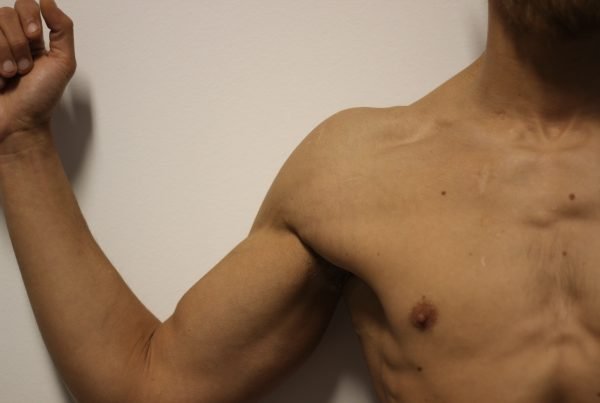

Schouderklachten

Schouderklachten

Schouderklachten zijn een alomtegenwoordig gezondheidsprobleem dat mensen van diverse leeftijden en achtergronden treft. Deze klachten…